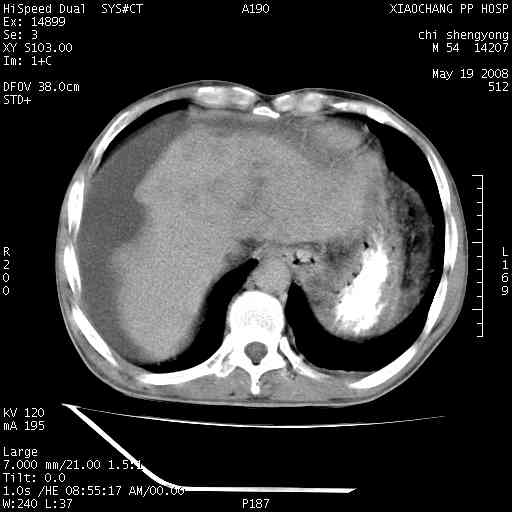

以下是引用zjzjr在2008-5-21 10:52:00的发言:[br]肝左叶巨块型肝癌伴门静脉左支瘤栓形成.肝硬化、腹水,胃底静脉曲张,脾术后改变。

以下是引用随光逐影在2008-5-21 16:20:00的发言:[br]1)肝左叶肝癌伴门静脉左支瘤栓形成,腹膜后淋巴结转移。2)肝硬化、腹水、胃底静脉曲张。3)胆囊炎。4)脾脏缺如,为切除术后所致。